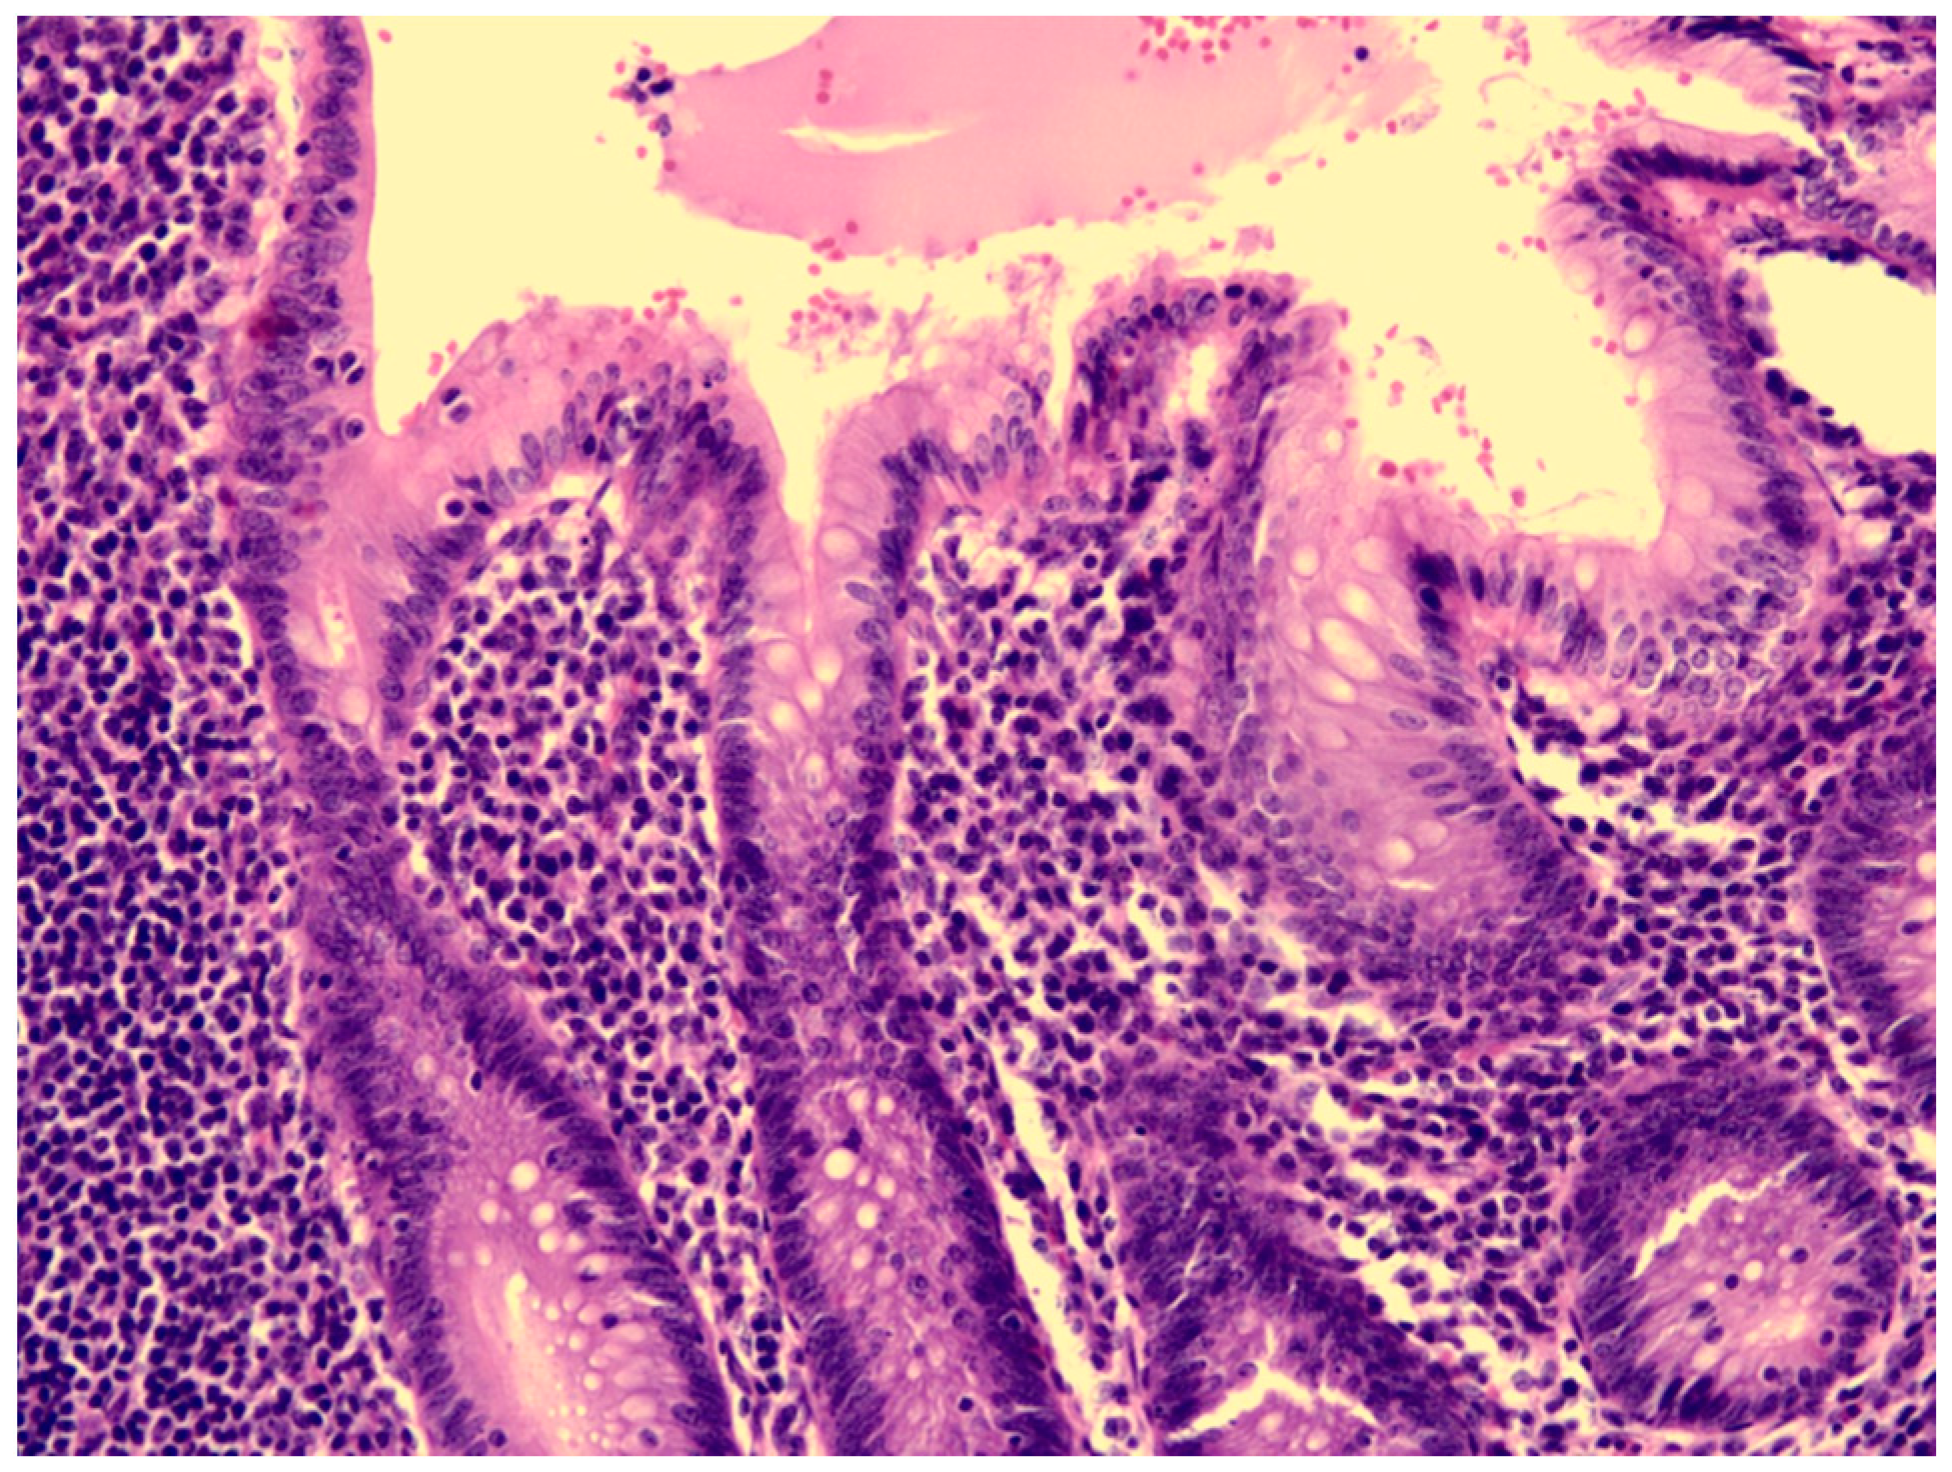

Figure 3.

The mucosa of the appendix was intact, without erosion or ulceration.

KD may present with appendicitis, though it is a rare presentation. There is little information about KDSS with appendicitis. Two possible cases are reported after reviewing the literature (Table 1). Taddio, A. et al. reported a patient with KDSS undergoing a surgical intervention due to a clinical and radiological diagnosis of appendicitis [9]. However, post-operative findings showed thickening of the ileal loops, consistent with mesenteric vasculitis. Gamez-Gonzalez, L.B. et al. reported another possible case [1]. One patient underwent a surgical intervention as a result of a clinical and radiological diagnosis of appendicitis and septic shock. The postoperative findings were positive only for peritoneal cavity effusion. In our case, the clinical diagnosis of appendicitis was made. The pathology report of the appendix showed the presence of neutrophils in the muscularis propria of the appendiceal wall, which was compatible with appendicitis. However, the mucosa of the appendix was intact, which may imply that the inflammatory source was not the appendix.